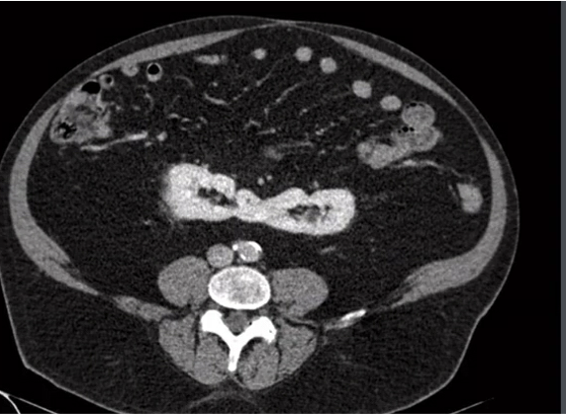

masses with 3 or more septa are NOT multisepated but they are multiLOCULATED

two most common multilocated masses in an adult?

multilocular cystic nephroma and multilocular RCC

you cannot tell the difference between the two on imaging